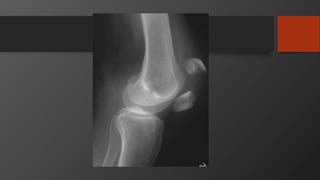

Tibial Plateau Factures

Anatomy

• Consist of medial and lateral

plateau

• Medial larger

• Medial lower (concave)

• Medial bone harder (thus

less likely to fracture)

• Lateral higher (convex)

• Lateral cartilage thicker

Tibial Plateau Fracture

• Mechanism

• Varus/valgus load with or without axial load

• Like fall from height